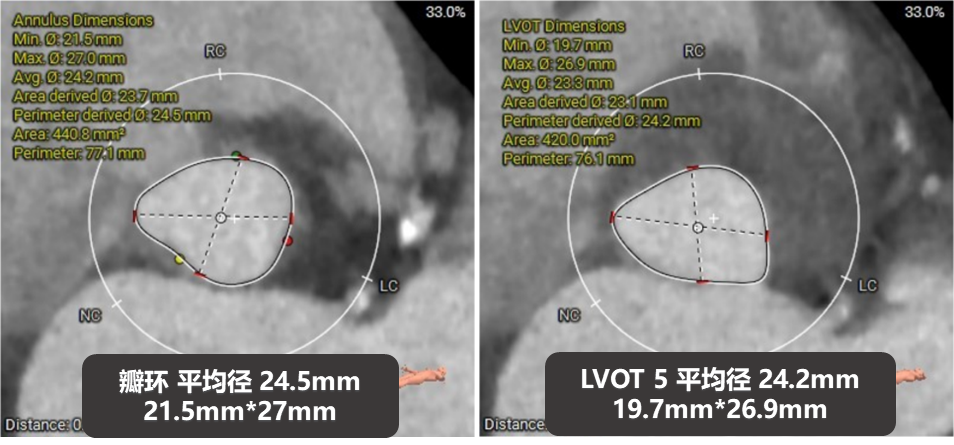

主动脉根部评估

四叶式主动脉瓣,右无间窦体发育较小且窦底高于瓣环平面约6mm;

AAO轻度扩张,Max>43.1;

瓣环上结构测量

收缩期瓣上结构

收缩期瓣上可提供4~6mm筒状区域。

舒张期瓣上结构

舒张期瓣上5mm内区域均小于收缩瓣环径;

该病例的瓣上结构可提供的辅助锚定区域较长,有利于瓣膜的辅助锚定。

冠脉高度、瓣叶长度及左室内径

左冠高度:7.1mm;右冠高度:13.4mm;

左冠-窦底距:9.7mm;右冠-窦底距:14.4mm;

左冠瓣长度:12.3mm;右冠瓣长度:14.8mm;

左冠水平高度较低,开口内径较大,瓣叶略长,LCC至对合缘距离约30mm,存在一定左冠阻塞风险。

左室室间隔基底部肌性凸起,增加了流出道锚定有利因素。